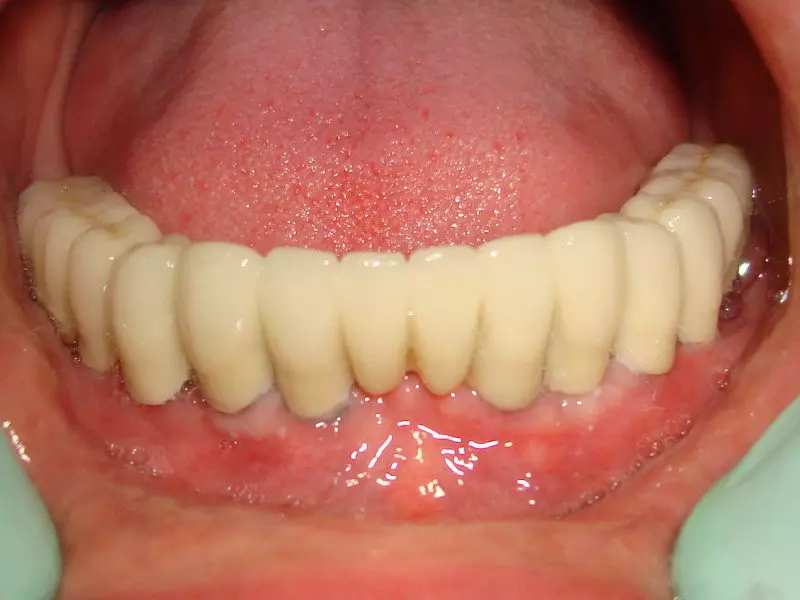

These technology also can be used for designing the CAD CAM prosthesis made on dental implants.